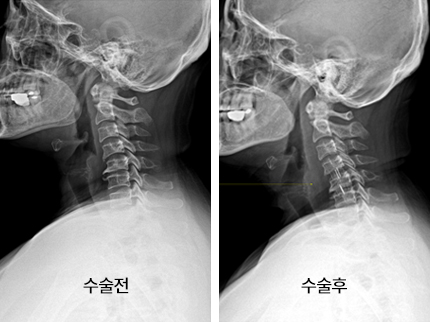

시술로써 눈에 띄게 질환을 현저히 치료하시는 것이 아니라 염증을 보완하고 통증을 낮추는 것이 포인트입니다. 이러한 방식으로 비 수술적인 치료를 3개월 이상 넘었음에도 불구하며 증상이 호전을 보이지 않으신다면 목디스크 치료방법 중 수술적 치료를 고심해야 하더라고요. 인공디스크를 투입하기 위함으로 절개를 통하기에 디스크를 제거하며 뼈를 하나로 유합 시켜서하는 것과, 내시경 수술로 빠져 나온 수핵 자체만을 제거시켜서하는 방법이 있다고하고요.

목디스크 수술

수술 방법에도 많은가 있다고 하는데 개괄적으로 설명을 하면 목을 절개해 망가진 디스크를 제거한 뒤 뼈를 하나로 유합하는 방법, 인공 디스크 투입술, 내시경을 활용해 바깥으로 빠져나온 수핵을 없애는 수술법 등이 있다고 합니다.